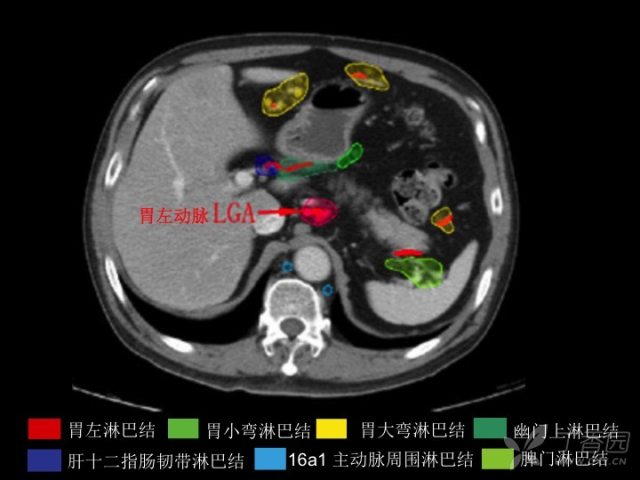

近期,笔者在 Oncotarget 上看到一篇非常实用的文献,研究者回顾性分析了 255 例胃癌伴有淋巴结转移患者的初始影像,目的是为了更好的确定胃癌新辅助放疗的 16 站淋巴结的分布和转移风险度。根据 2846 个淋巴结(每站淋巴结转移个数为 31~599)绘制了胃癌 16 站淋巴结引流区密度分布图谱,为术前新辅助放疗淋巴结引流区 CTV 确定提供了参考模板。

本篇除了对胃癌新辅助放疗靶区勾画有指导意义外,同时也可以帮助大家复习上腹部 CT 解剖影像以及淋巴结引流区分布。